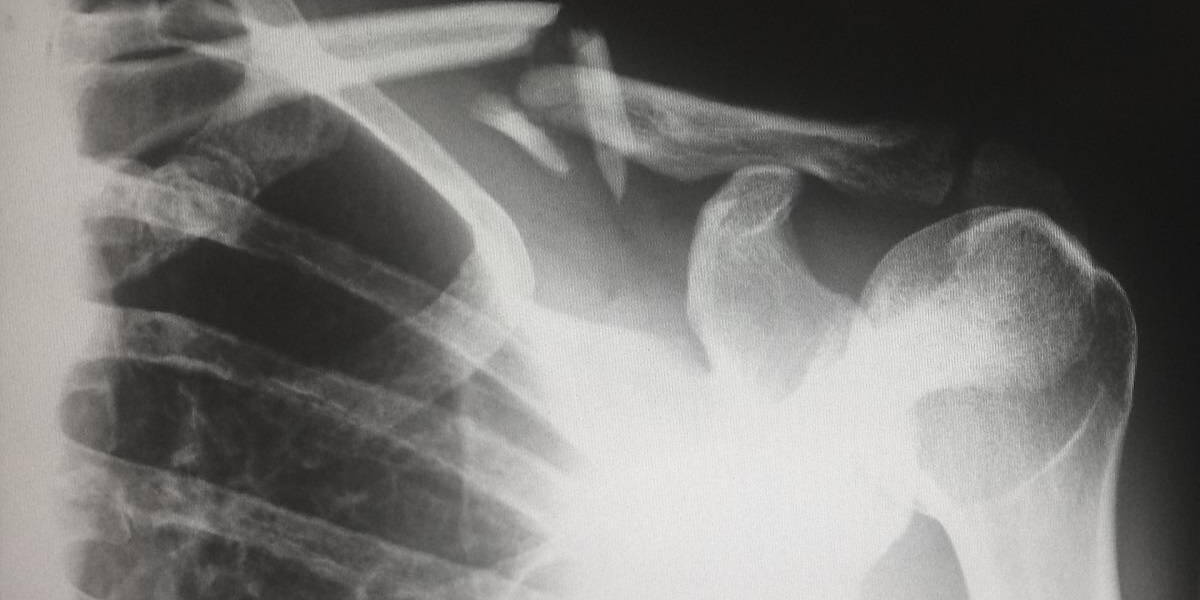

Sinds 15 maart hebben patiënten met een MijnOLVG-account toegang tot de beelden die horen bij een radiologieverslag. Daarmee is OLVG een van de eerste ziekenhuizen in Nederland die deze functie aanbiedt. Voorheen konden patiënten namelijk alleen het verslag van een radiologie-onderzoek bekijken in MijnOLVG. Wilden ze de beelden zien die tijdens het onderzoek werden gemaakt, dan moesten ze de radiologiebeelden opvragen via het Patiënten Servicepunt.

De radiologiebeelden die de patiënt nu kan bekijken in MijnOLVG staan niet op zichzelf. Deze horen bij een verslag en een conclusie van de radioloog. Zodra het verslag via MijnOLVG is vrijgegeven door de zorgverlener, kunnen de beelden bekeken worden.